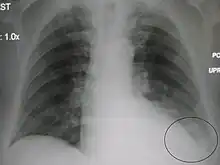

A black and white X-ray picture showing a triangle white area on the left side. A circle highlights the area.

A chest X-ray showing a very prominent wedge-shape bacterial pneumonia in the right lung